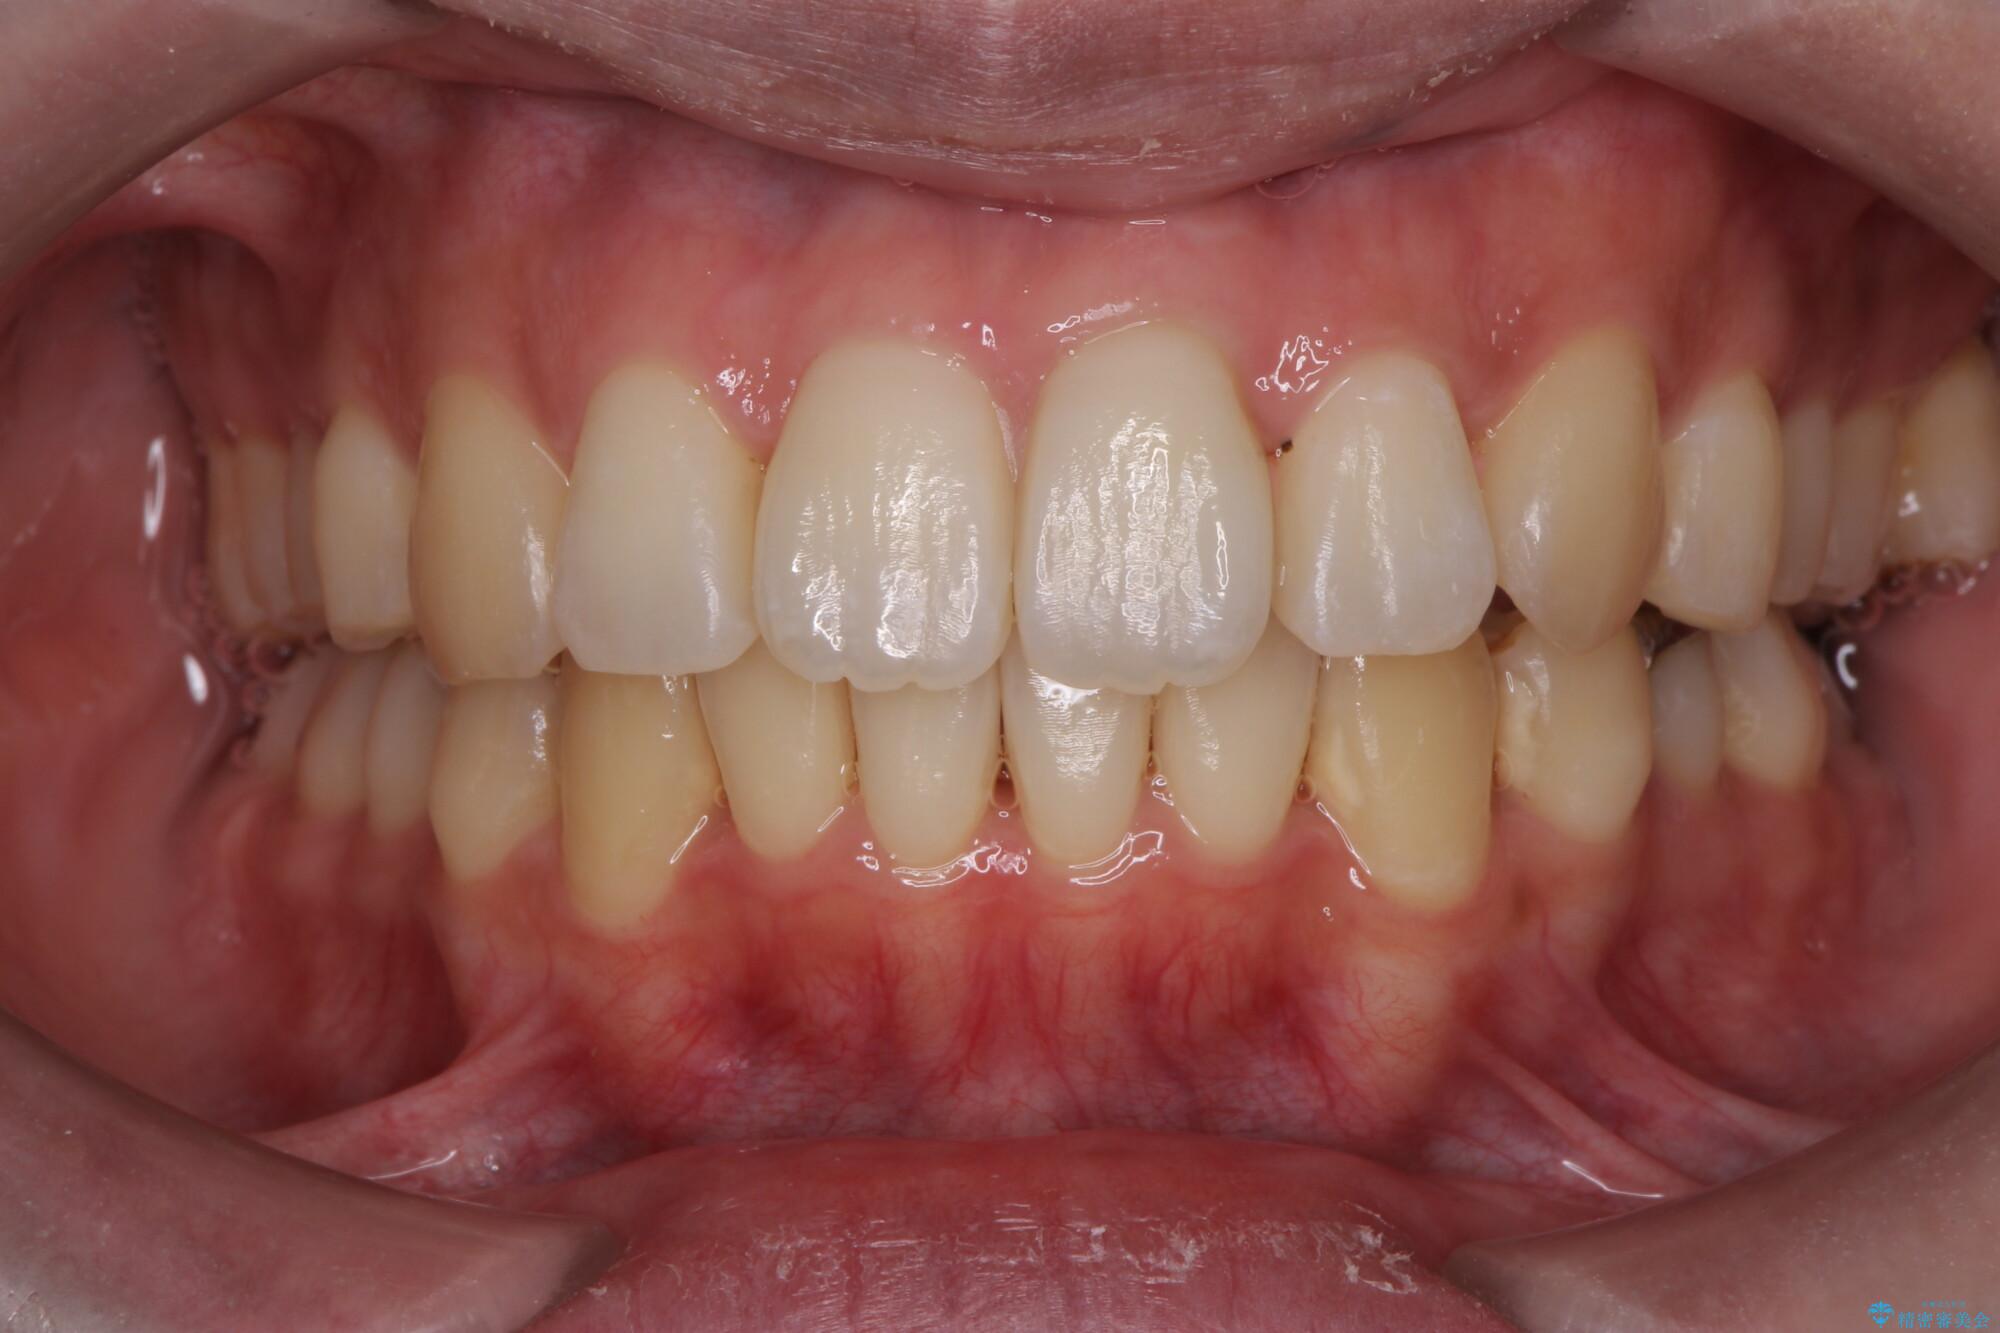

前歯のガタつきの改善を主訴にご来院されました。 特に犬歯の傾きが気になるとのことでした。

犬歯がかなり手前に傾いていましたが、ガタつきはそれほど強くないため非抜歯でマウスピース矯正が可能と判断しました。

治療前

気になる犬歯のガタつきをマウスピース矯正で改善 治療前画像 気になる犬歯のガタつきをマウスピース矯正で改善 治療前画像 気になる犬歯のガタつきをマウスピース矯正で改善 治療前画像 気になる犬歯のガタつきをマウスピース矯正で改善 治療前画像